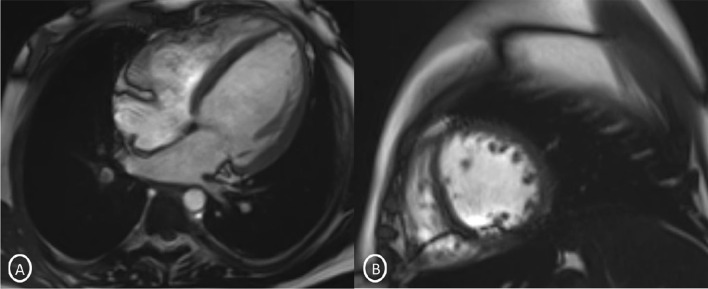

A 19-year-old female had presented to our Emergency Department, complaining of sudden severe chest and epigastric pain since 1 day, which was associated with sweating. The pain was radiating to neck and left arm. The pain did not relieve on rest but subsided on medications. Similar episodes were also reported in the past few days, however, with less severity. The patient confirmed to not having shortness of breath, palpitation, syncope, dizziness, nausea, emesis, fever, or cough. There was no history of any previous cardiac ailment/surgery/other identifiable cardiovascular risk factors or any other history of infection. There is no evidence to suggest chest wall trauma. There is no history of comorbidities or any history of smoking. There is no significant family history or any similar past history. Upon admission, patient was conscious, alert with heart rate of 86 bpm, blood pressure measuring 110/60 mm Hg, 97% oxygen saturation at room air, temperature of 36.4 °C, and respiration rate of 15 breaths/min. The cardiac biomarker troponin T levels were extremely raised, measuring 50,000 pg/ml, and CK-MB was raised, measuring 111U/Lt. Laboratory findings showed that inflammation markers were normal, C-reactive protein (5.8.0 mg/L) and D-dimer (94 ng/mL). Other laboratory findings such as lipid profile, complete blood count, electrolytes, fasting blood glucose, HBA1c, and renal and liver function tests were normal. Cardiac auscultation showed normal S1, S2 without murmurs or pericardial rub and any sign of heart failure. Initial ECG revealed ST segment elevation in the leads I, aVL, V4, V5, and V6 leads, normal sinus rhythm (60 beats per min) without any other abnormalities (Fig. 1), which was resolved by day 3. Arrhythmias were not found during continuous cardiac monitoring. Echocardiogram showcased an ejection fraction of the left ventricle to be 60%, whereas the echocardiographic metrics were not very significant. Patient was then treated as ACS with a salicylate-based nonsteroidal anti-inflammatory drug (NSAID), anticoagulants, and anti-thrombolytics. CMR was done on 3 T MRI machine with acquisition including T2/STIR Dark blood four-chamber long axis; CINE images in short axis, long axis, RVOT, and LVOT; and early dynamic gadolinium enhancement images and delayed gadolinium enhancement in PSIR images. T2/STIR Dark blood sequences showed T2 hyperintensity in the subepicardial region along left lateral wall (Fig. 2A, B). There was associated mild global hypokinesia with mildly reduced ejection fraction/systolic function (Fig. 3A, B). Patchy delayed gadolinium enhancement of intramural, subepicardial as all tans-mural enhancement with non-involvement of the subendocardium (suggesting a non-ischemic pattern) in multiple segments of cardiac basal (Fig. 4A, B), mid cavity (Fig. 5A, B), and apical cavity—with predominant involvement of lateral (Fig. 6A, B) and inferior wall segments in the basal cavity. There were no signs of infarction of myocardium; therefore, the patient was diagnosed with acute myocarditis (based on Lake Louise Criteria for Acute Myocarditis). Further, viral and autoimmune workups results were found to be negative. It included hepatitis (B, C), human immunodeficiency virus, Coxsackie virus, COVID-19, cytomegalovirus, Epstein–Barr virus (EBV), and Parvovirus B-19. On further analysis and detailed relevant history workup, the patient admitted to using cannabis for the past 1 year with last exposure being 3 days before admission. On the basis of detailed clinical history, findings on CMR with other negative viral markers, and possible etiological factors, a final diagnosis of myocarditis presumed secondary to marijuana/cannabis toxin abuse was made. Patient was released from the hospital on the seventh day with advised conservative treatment. The patient was counseled to abstain completely from cannabis or related drugs. Patient was advised to repeat a CMR control, three months later. A 3–4-month restriction on high-intensity activity was also given to the patient following discharge.